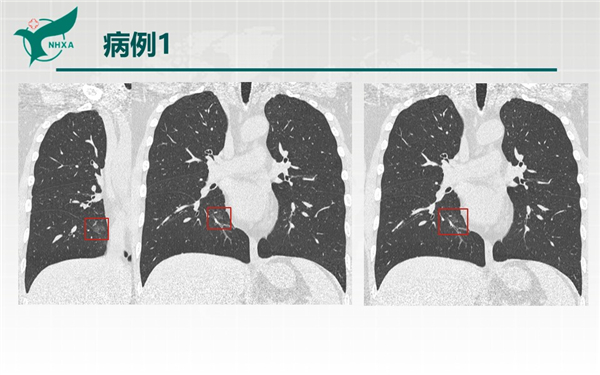

【病例分享】新型冠狀病毒肺炎3例(西安市第九醫(yī)院)

幻燈片6.jpg